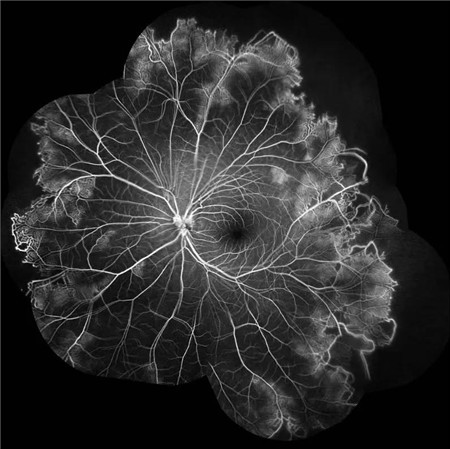

视盘附近的动脉和动脉分叉处出现瘤样动脉扩张,视盘充血,边界不清,引起视盘周围视网膜内硬性渗出;视盘周可有少量放射状出血。

静脉不规则扩张和血管鞘膜,周边部小血管广泛闭塞,交界处毛细血管扩张和异常吻合。

严重者可发生从周边到黄斑的血管闭塞和缺血、玻血、新生血管性青光眼,最终视神经萎缩。